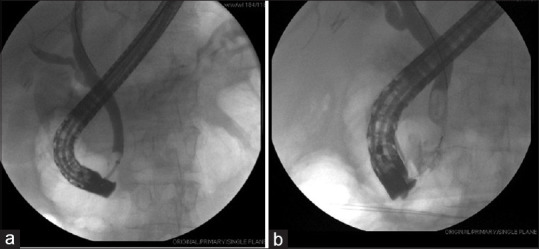

Abstract: Migration of cholecystectomy surgical clip into the common bile duct with subsequent stone formation is a rare phenomenon, one which may lead to complications including obstruction, pain, nausea, vomiting and fever. The mechanism of migration is largely unknown but may result from a combination of factors including necrosis, intra-abdominal pressure or poor surgical technique with migrated clip serving as a nidus for stone formation. We present a 55-year-old woman with clip-induced stone impacted at the distal common bile duct 12 years post-cholecystectomy and a review of the literature related to cholecystectomy clip stone formation. In addition, we reviewed relevant English language case reports and literature reviews by searching PubMed using search terms 'stone', 'clip', 'cholecystectomy' and 'biliary'. There was no limit to the date of publication. Our study found 68 unduplicated cases of clip-induced stones which had a wide range of onset and presenting systems. Further research is needed to identify risk factors, methods of prevention and benefits of early detection screening.